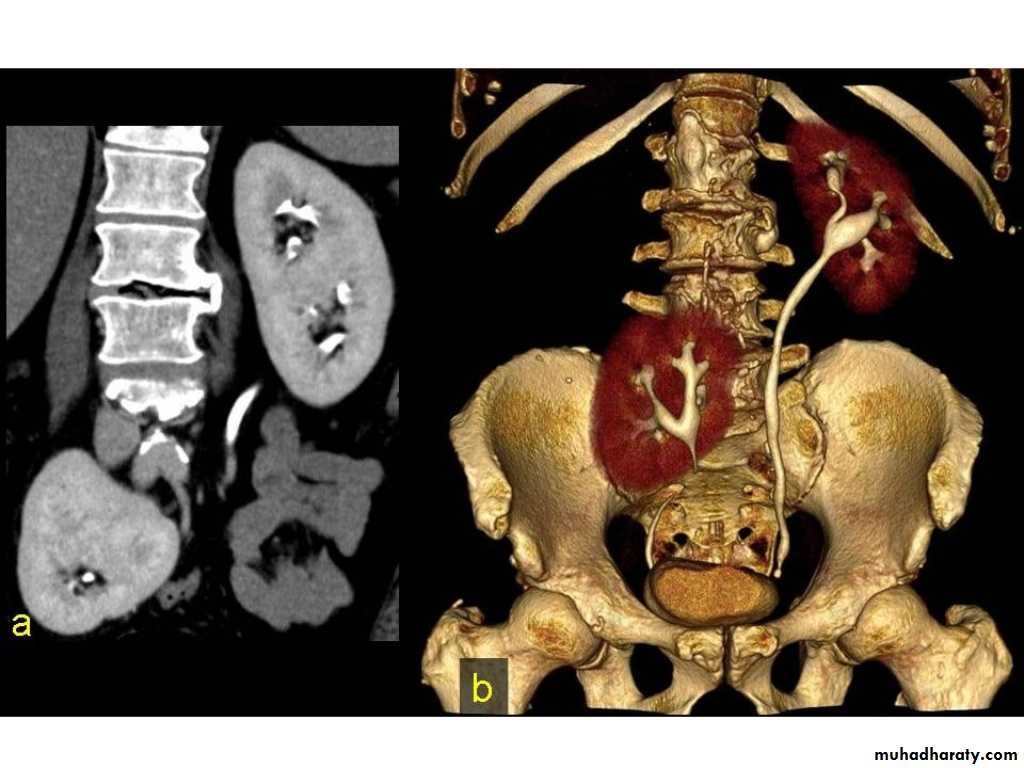

IVU shows

1. The kidneys at low position .2.Close to the spine with long axis parallel to the spine

3. Malrotation manifested by medially directed calyces.

4- The renal pelvis and ureters are anterior and lateral in position.

5- Hydronephrosis and calculi highly associated.